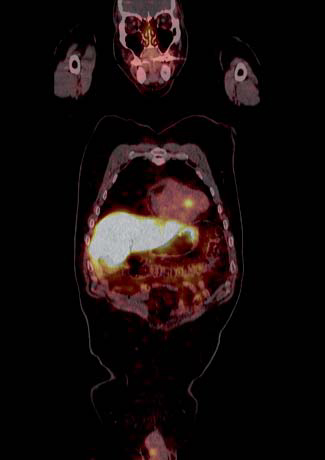

Insulinoma

Es un tumor endocrino del páncreas muy poco frecuente, se calcula su incidencia anual en 0,5-3 casos por millón de habitantes. Casi siempre está ubicado en el páncreas (1/3 en la cabeza, 1/3 en el cuerpo y 1/3 en la cola) aunque puede tener localizaciones ectópicas: duodeno, divertículo de Meckel, vía biliar, ovario y omento. Generalmente son pequeños: 40% son menores de 1 cm y 50% entre 1 y 5 cm y generalmente solitarios. Menos del 10% son múltiples, en cuyo caso debe descartarse síndrome de NEM tipo 1. Menos del 10% son malignos y 5% se presentan con metástasis, generalmente en el hígado o adenopatías regionales27 (Figura 10). Los insulinomas benignos y malignos suelen expresar receptores de somatostatina, el más frecuente es el subtipo 4 (80-90% de los casos), de moderada (10-50%) a gran intensidad (> 50% de las células tumorales) en los estudios inmunohistoquímicos. Los subtipos 1, 2 y 3 se expresan esporádicamente (40-50% de los casos) en los insulinomas benignos y malignos,generalmente en menos del 10% de las células neoplásicas. Los insulinomas benignos no expresan sstr 5 mientras que algunos malignos sí lo hacen28. Estos hallazgos están en línea con la experiencia clínica: aproximadamente el 50% de los insulinomas son positivos en la cintigrafía con pentatreotide y el tratamiento con radiopéptidos análogos de somatostatina (Lu177-DOTATATE o Y90-DOTATOC) es paliativo y sirve para ayudar al control de la hipoglicemia de estos enfermos29 (Figura 11).

Fusión SPECT/RM. Imágenes transaxiales de RM y SPECT con In111- pentatreotide.

Paciente con insulinoma metastásico. Se demuestra intensa sobreexpresión de receptores de somatostatina en metástasis hepáticas múltiples.